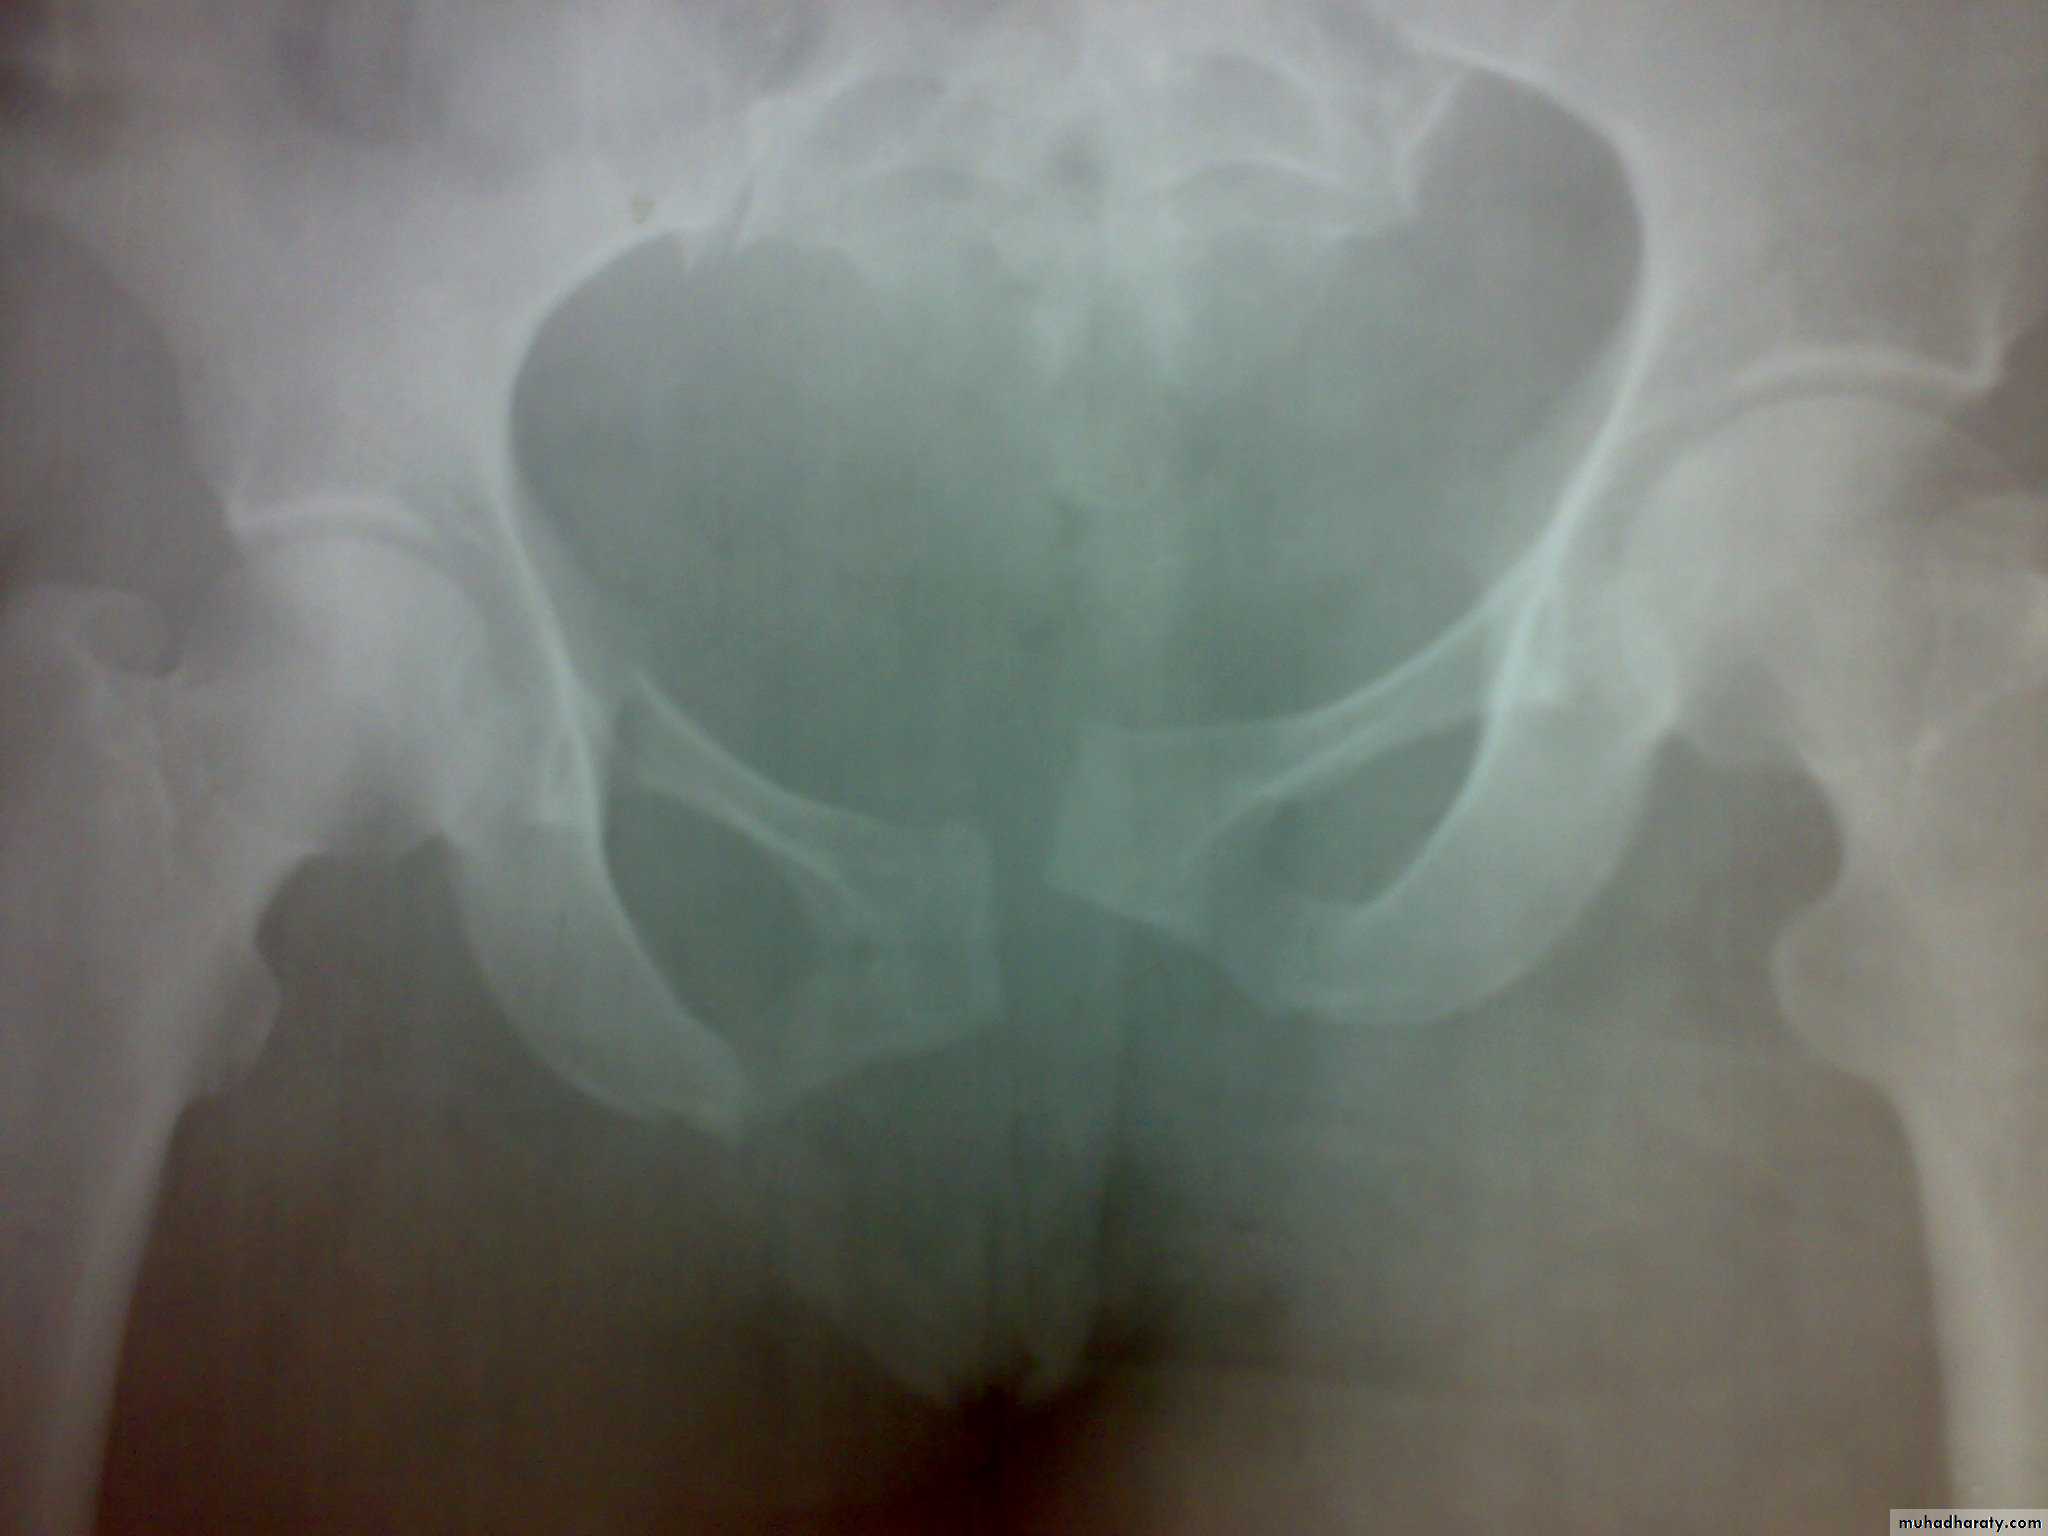

Fractures with a broken ring

Stable ring fractures

Undisplaced fractures of one or two ipsilateral pubic rami.

Fractures of the blade of ilium.

Fractures of acetabulum.

Fracture pubic ramai

Fracture pelvic blade